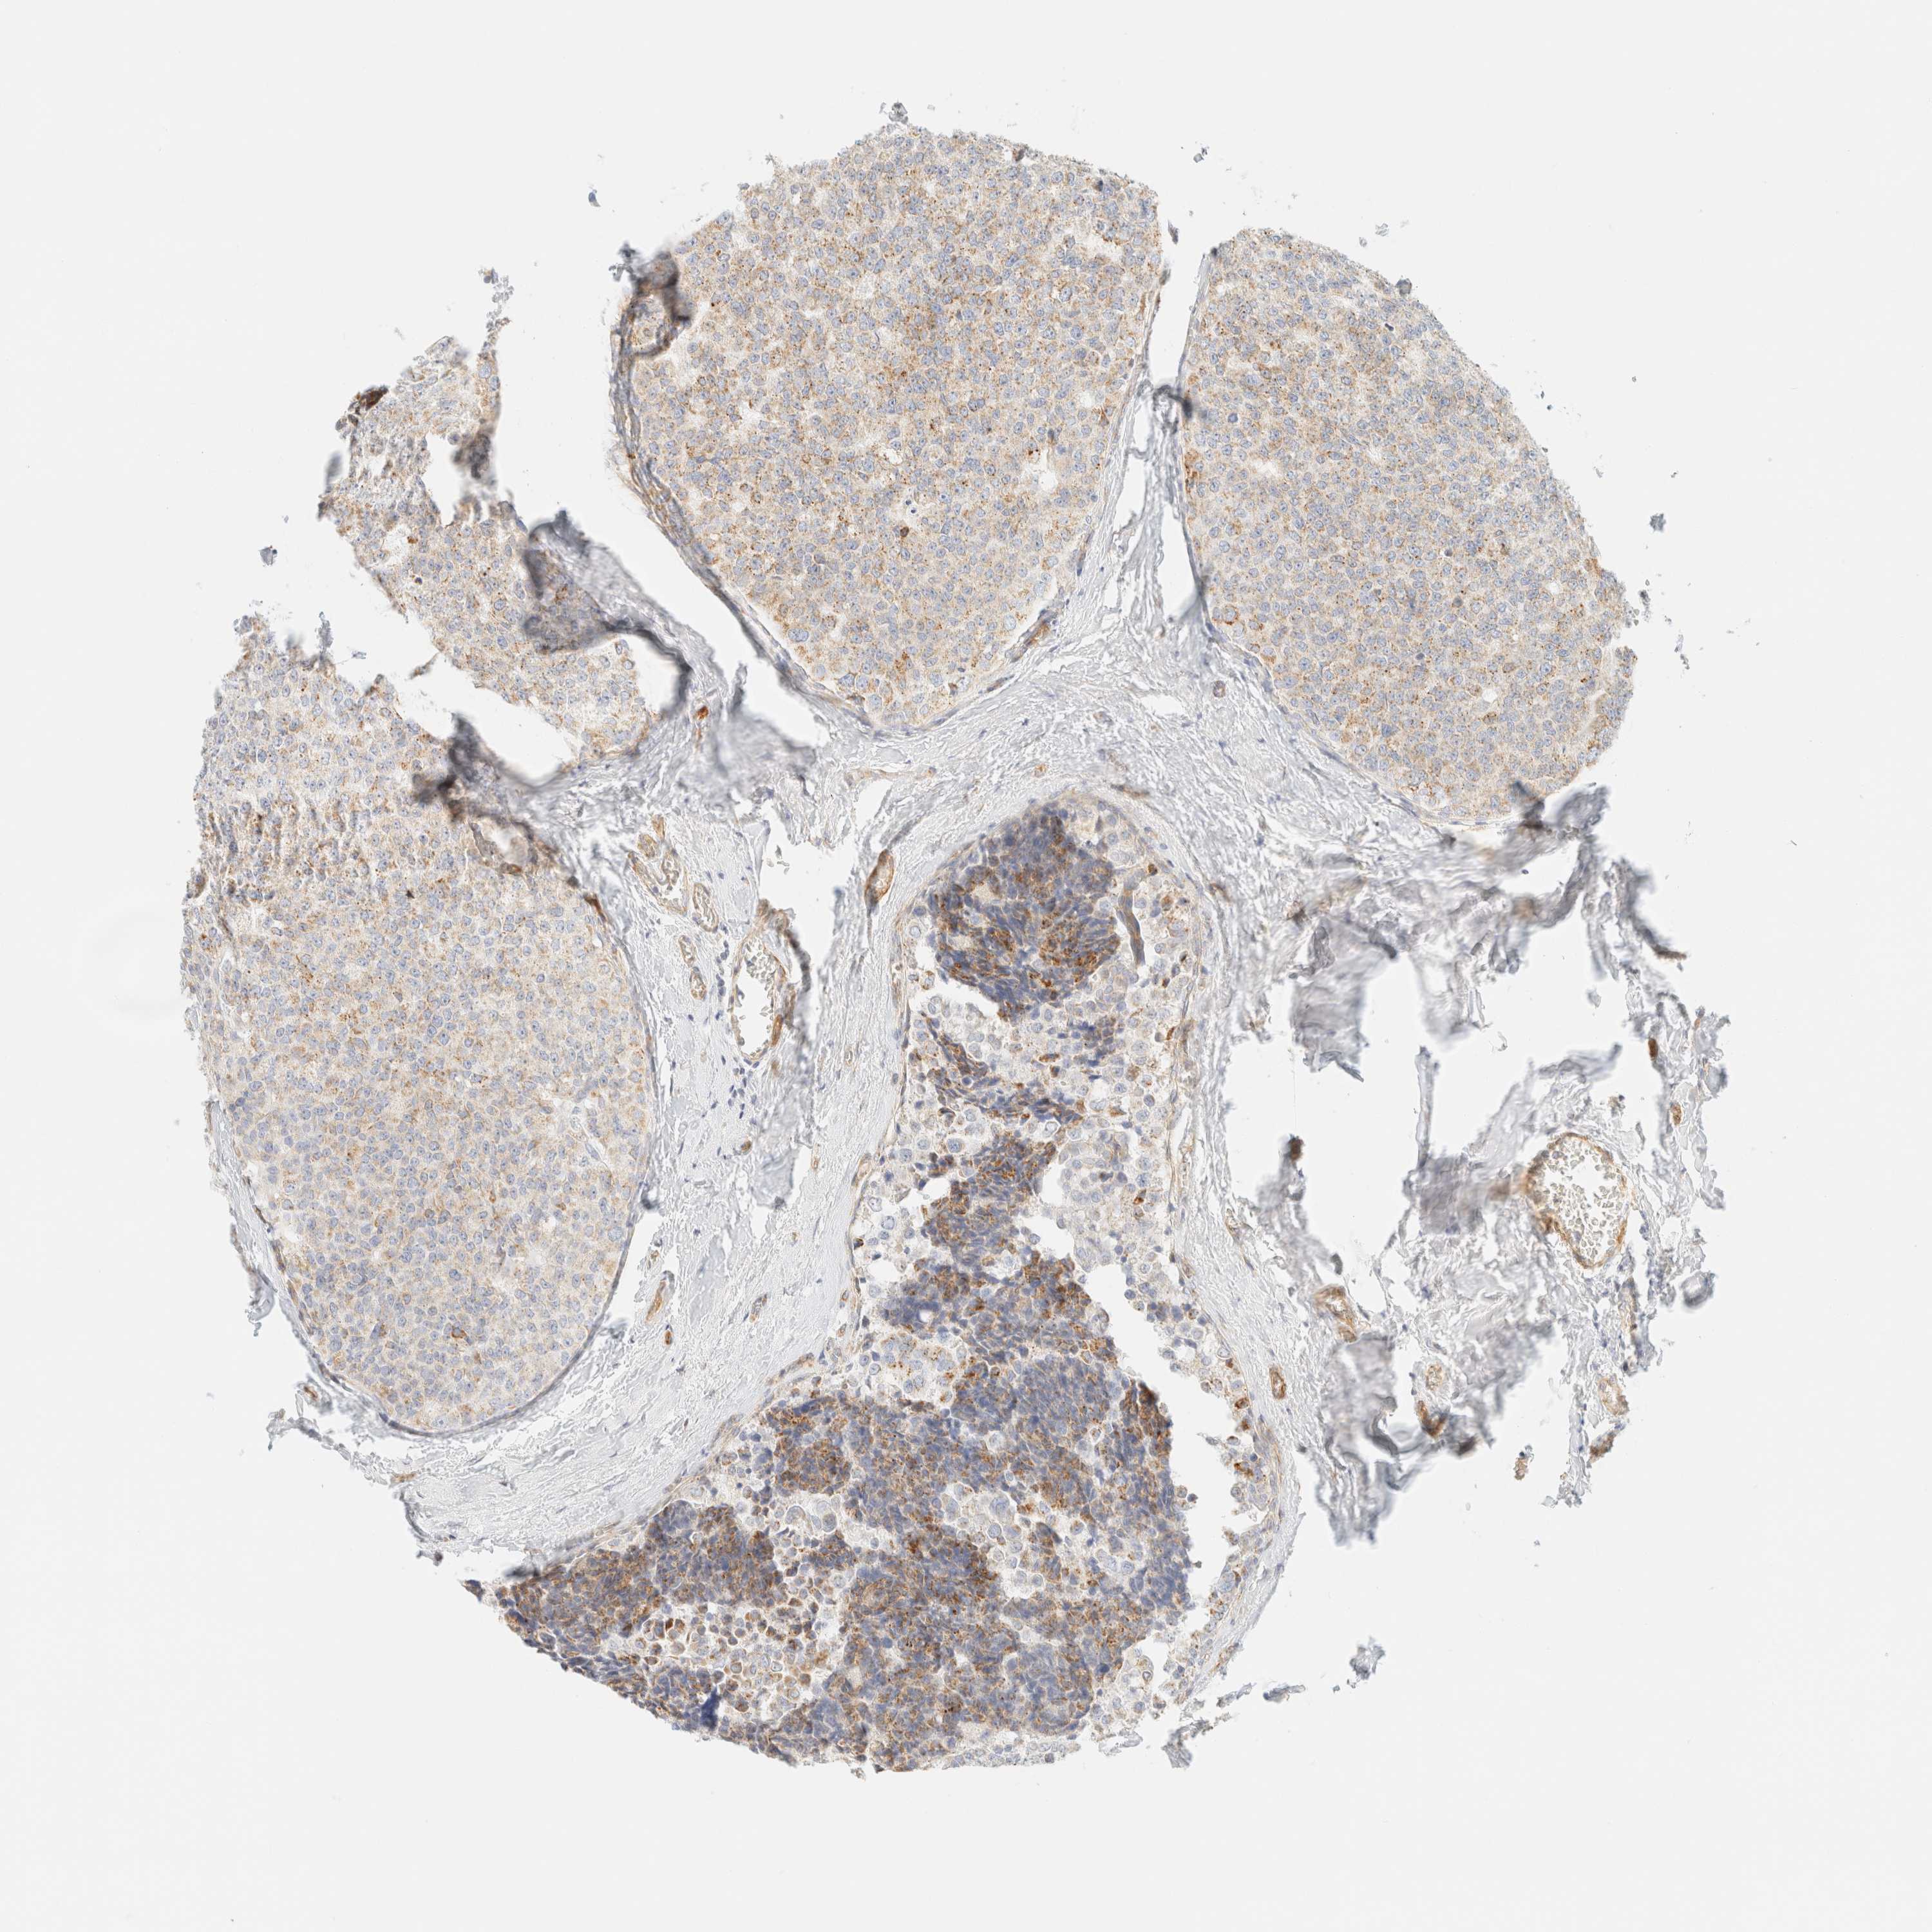

BRCA TCGA BRCA VALIDATION PROTEIN EXPRESSION

ANTIBODIES

AND

VALIDATION